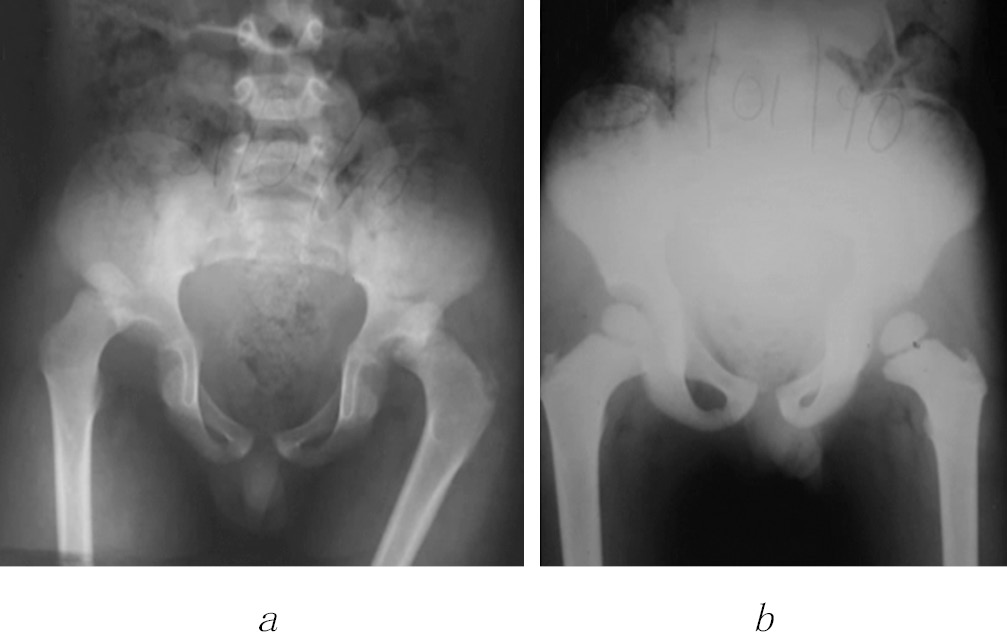

X-ray were obtained, they revealed incongruence of both coxofemoral joints, with posterior displacement of both femoral heads, without solutions of bone continuity (Fig. 1).

Fig. 1. Initial X-ray. Anteroposterior pelvis showing bilateral posterior hip dislocation (a); immediate postreduction X-ray. Pelvis with reestablishment of both coxofemoral joints (b)